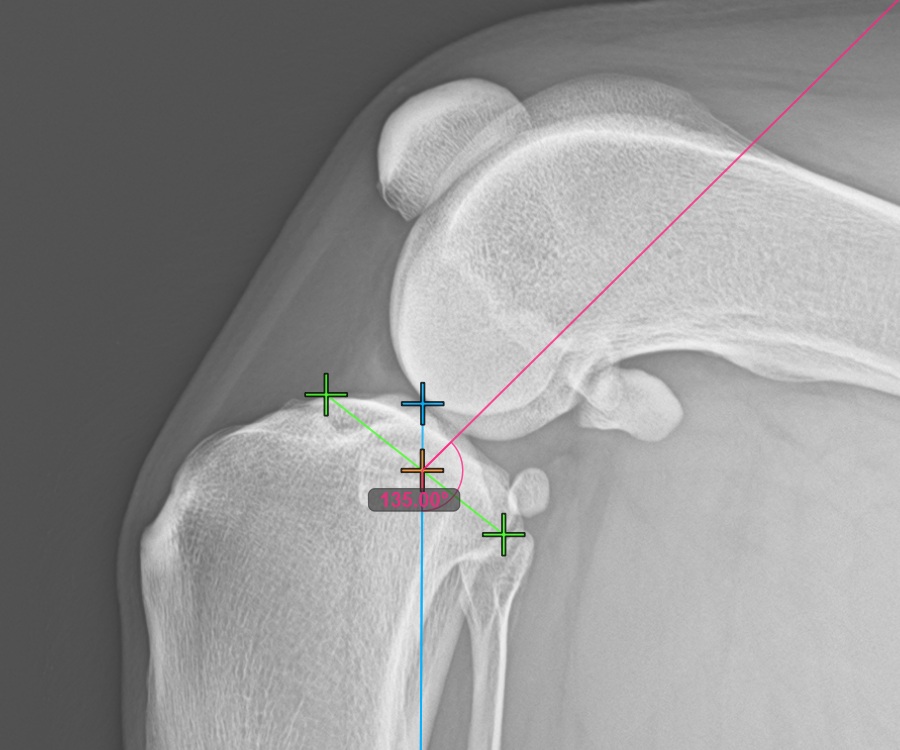

Mark the most caudal point of the tibial head to continue the measurement. Additionally, the software automatically draws a fixed angle measurement of 135°, with the intersection between the long axis of the tibia and the line connecting the most cranial and most caudal point acting as the vertex point for the angle.

The image below depicts the usual placement of the most caudal point on the tibial plateau.